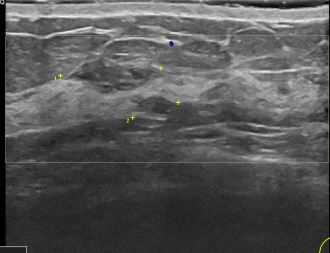

상기환자는 외부검사이상소견으로  내원하신 40대중반

여성분으로 의심스러운 좌측혹 조직검사 시행해 상피내암 으로 진단되었습니다